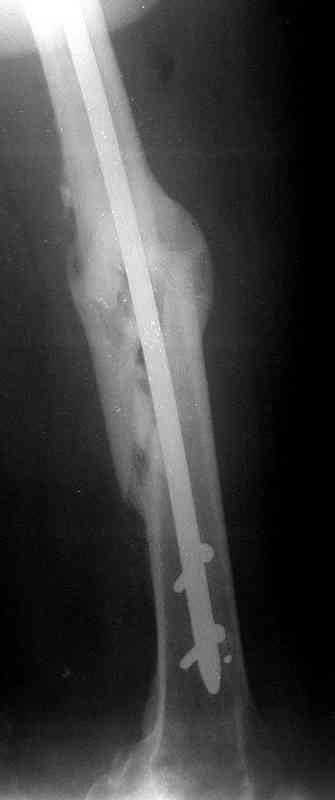

месяцев дистракции укорочение левого бедра удалось полностью устранить. 22.02.00, т.е. через 2 месяца после повторного остеосинтеза, больному произведено дистальное блокирование штифта двумя винтами и демонтирован аппарат Илизарова. В течение 2 недель после операции больной ходил с помощью костылей, потом 2 недели с тростью. Опороспособность и функция оперированной конечности полностью восстановились через 4 недели после операции.

Фиксаторы удалены через 12 месяцев после операции, выполненной по поводу замедленной консолидации перелома бедра с его укорочением.

На финальных снимках видно - сращение прям таки железное. Если Вы не устали отвечать, осмелюсь задать еще вопрос - что-то принимал пациент в целях ускорения сроста (кальций, режим питания). Интересны также вопросы восстановления функций конечности - в какой период были рекомендованы группы упражнений для восстановления основных групп мышц?